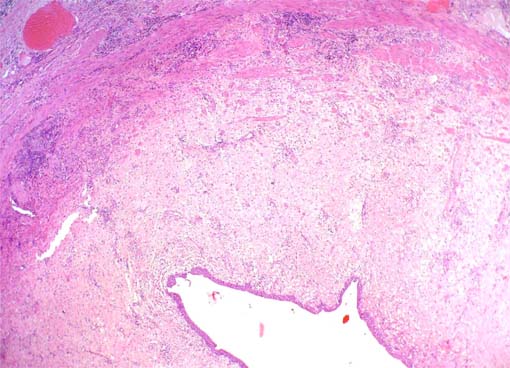

Figura 1.

Primera biopsia renal, a los seis meses post-trasplante. Rechazo agudo

mediado por células T; no hay lesiones arteriales. Izquierda: H&E,

X200; derecha: tricrómico de Masson, X400.